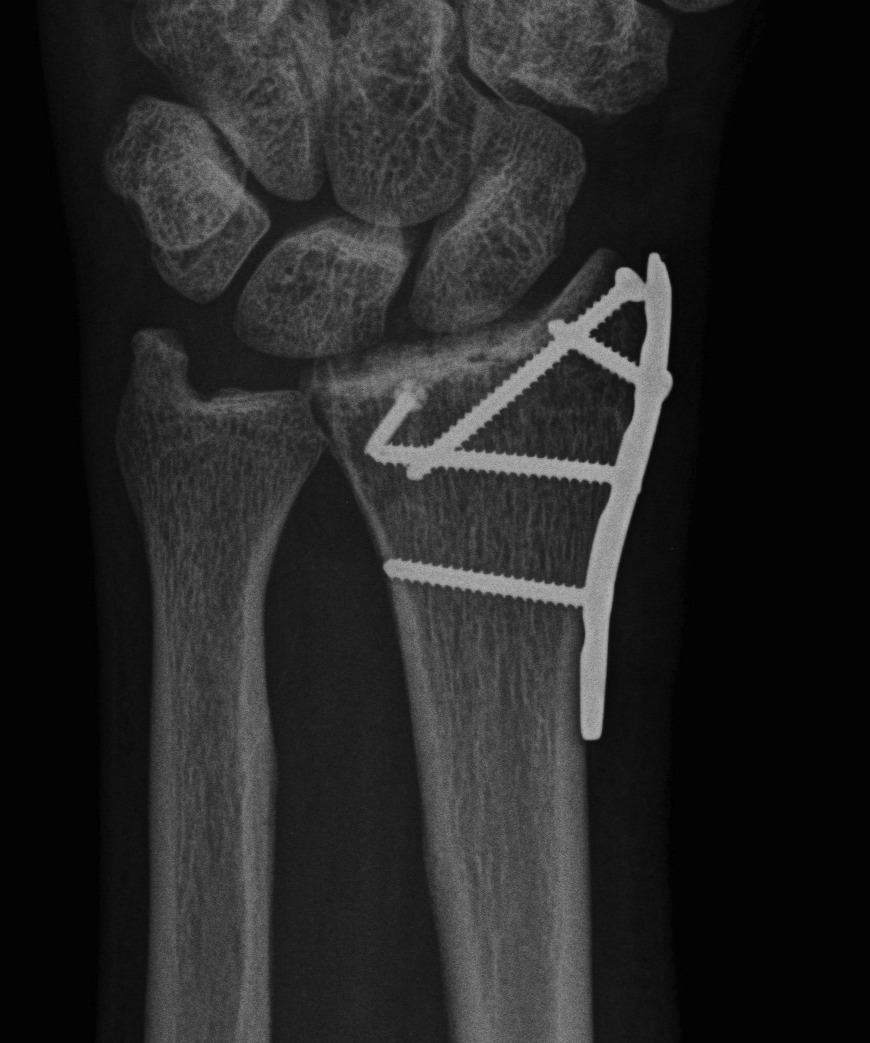

Dislocated Radiocarpal Joint Dislocated Radiocarpal Joint AP

Dorsal Radiocarpal Dislocation ORIF 1Dorsal Radiocarpal Dislocation ORIF 2